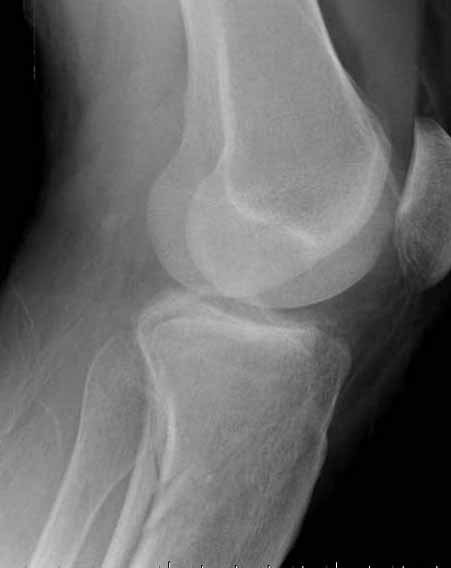

"участок некроза кожных покровов (см. фото), поэтому латеральная мыщелковая пластина не подойдет, а медиальных пластин у фирм-производителей нет. Пациент может приобрести современный имплант, но какой?"

Двухколоннный перелом тибиал плато с вовлечением проксимального диафиза. Внутрисуставной компонент без смещения, и такой перелом можно лечить любым из описанных методов, о которых говорят наши коллеги.

Как понял, аппарат Илизарова не рассматривается предпочтительным для фиксации методом, хотя на фоне отека было бы идеальным для данного перелома. Для пластины требуется идеальная кожа, иначе наличие “суперсовременных имплантов” не поможет, и могут развиться серьезные осложнения.

В основном пластины рассчитаны на латеральную поверхность, потому что с латеральной стороны больше мягкотканая подушка, а также через латеральную колонну проходит ось конечности, что немаловажно в удержании оси от деформации.

Частая ошибка, когда фиксацию двух колонного перелома проводят одиночной пластиной, т.е с одной стороны, и такая фиксация не удерживает, происходит вторичноое смещение. Необходимо нейтрализовать второй пластиной или дополнительным наружным фиксатором.

Кстати, коллеги правы для уточнения характера перелома надо делать Компьютерную Томографию.